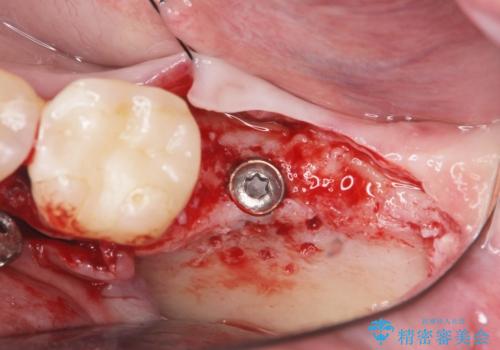

歯の抜去を行い、骨の造成を含めたインプラントによる咬合機能の回復を図ります。